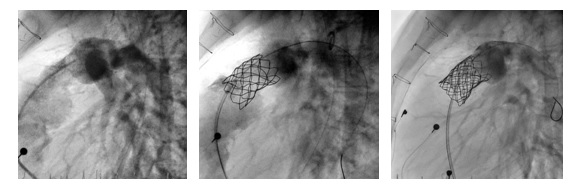

Pacjent 14-letni z miernym zwężeniem drogi odpływu prawej komory i narastającą niedomykalnością płucną, po operacji Fallota z rekonstrukcją połączenia prawej komory z tętnicami płucnymi homograftem płucnym 18 mm. Wskaż sposób leczenia jaki zastosowano: